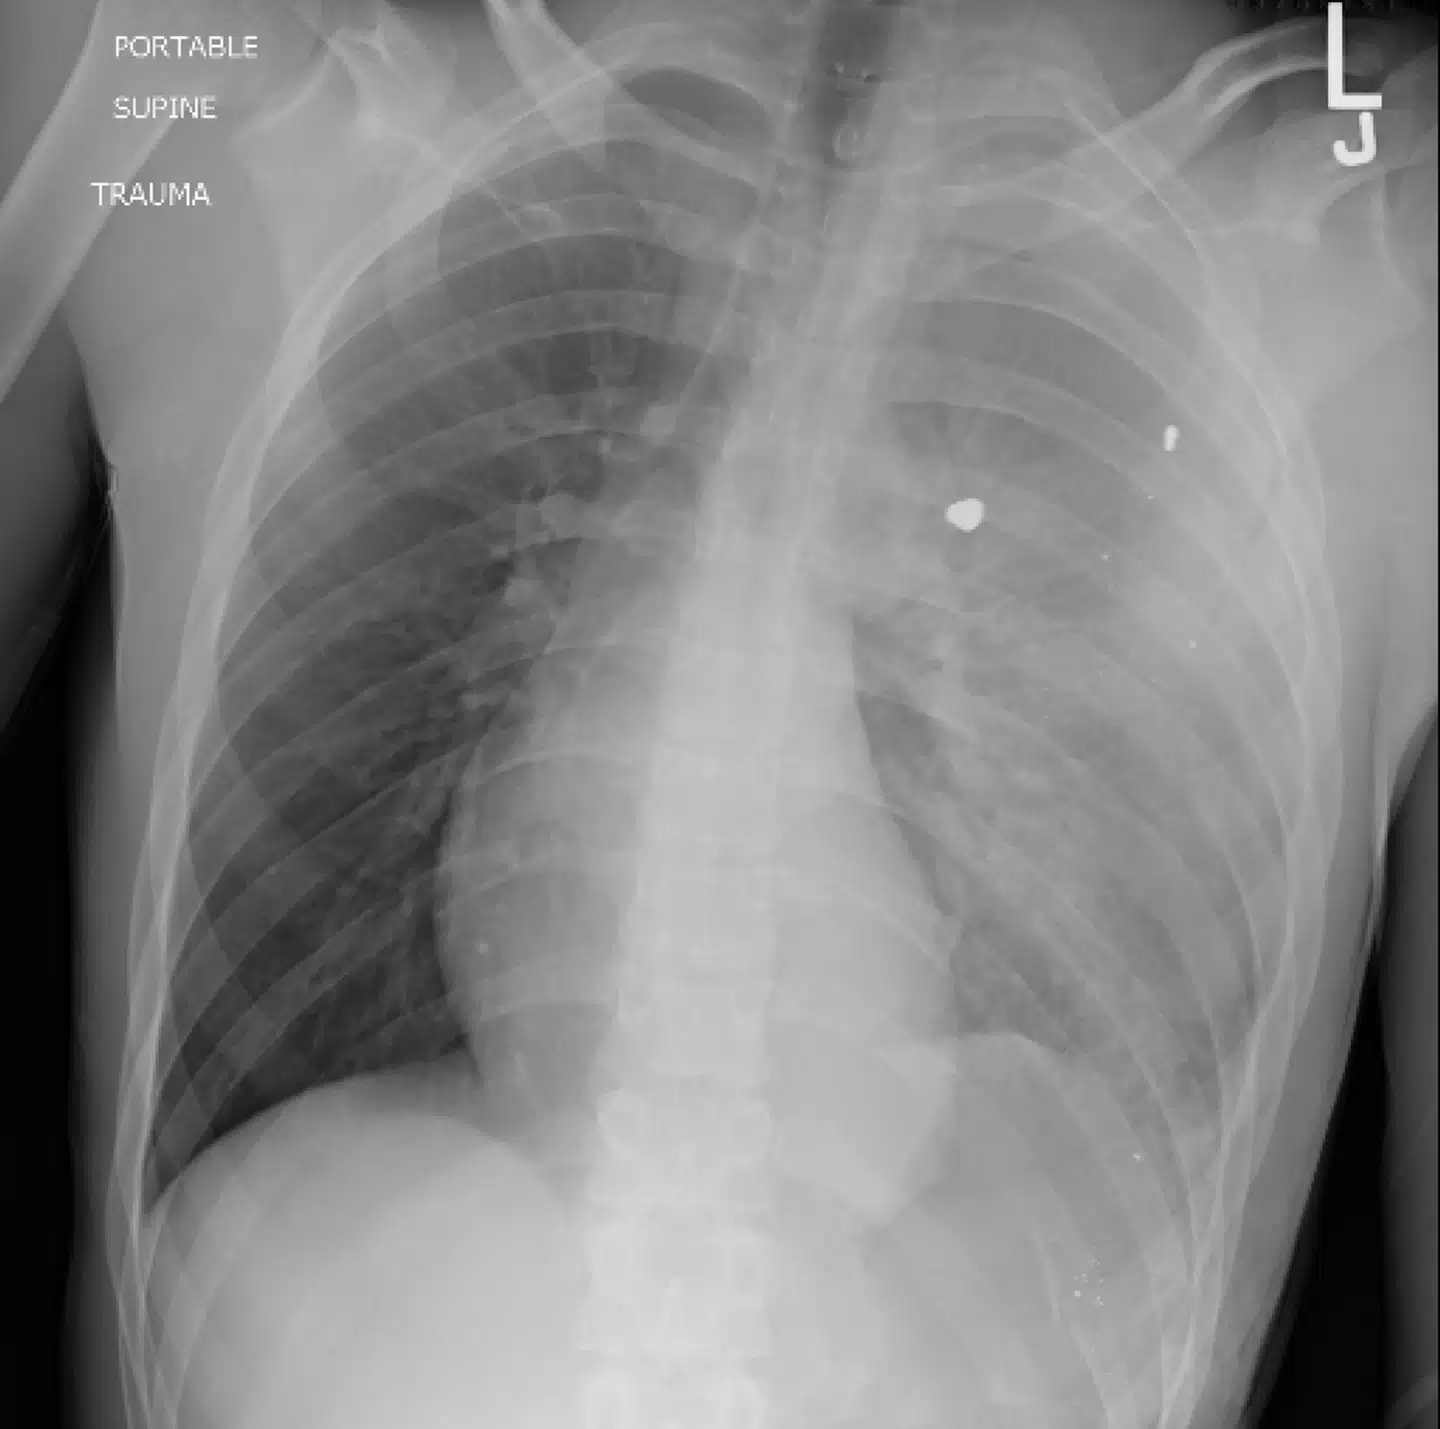

En læge lagde et røntgenfoto af en lille drengs bryst op på Twitter og fortalte, at drengen led af den hyppigste dødsårsag blandt amerikanske børn. »Hvad er diagnosen,« spurgte han i det virale tweet.